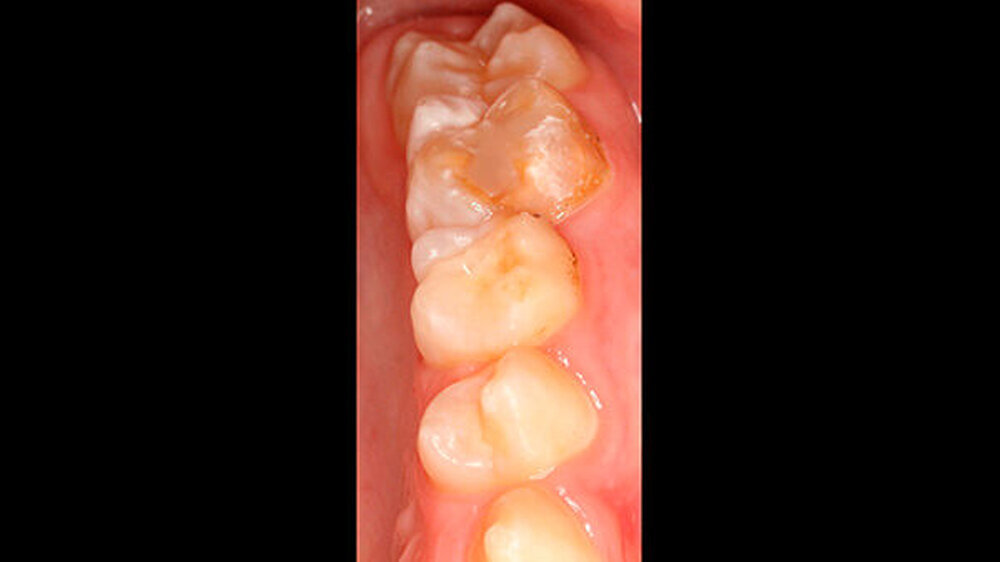

Der vor wenigen Jahren extrahierte Molar war der 16, anschließend war es im Laufe der Zeit im ersten Quadranten zu einer verhältnismäßig gleichmäßigen Lückenbildung gekommen. Der Zahn 17 war weitestgehend aufgewandert (Abbildung 2). Zahn 26 (Abbildung 3) wies eine umfangreiche adhäsive Restauration okklusal-bukkal auf. Zusätzlich dazu gab es aber auch weitere Areale mit veränderter Opazität von milchig-weiß (insbesondere palatinal) bis gelb-braun.

Zusätzlich wiesen beide Sechsjahrmolaren im Unterkiefer insbesondere im Bereich der Höcker (46) sowie der Höckerspitzen (36) ebenfalls Opazitäten auf, deren farbliche Veränderung von milchig-weiß bis hellbraun reichte. Zahn 46 war darüber hinaus mit einer erweiterten Fissuren-Versiegelung oder einer kleinen okklusalen Füllung versorgt. Das Trocknen der Seitenzähne mittels Luft rief ein geringfügiges Schmerzgefühl bei dem Patienten hervor, an Zahn 26 allerdings eine starke Sensibilität.